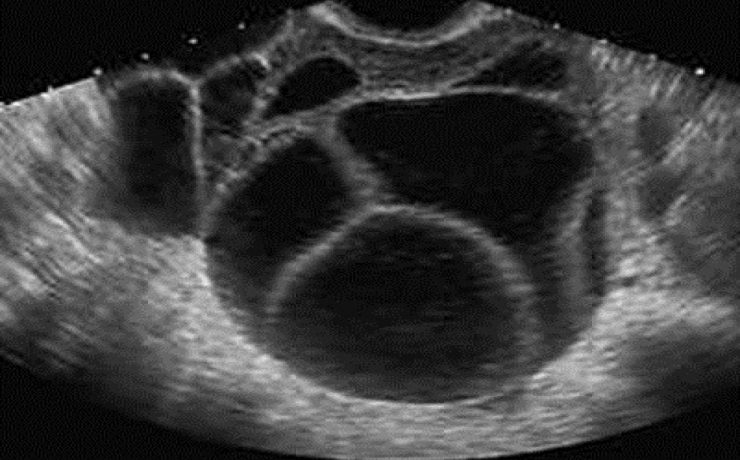

Las lesiones solidas clásicamente podemos diferenciarlas en alta, intermedia y baja celularidad. Las de alta celularidad son aquellos que poseen una gran cantidad de células, vasos edema y un rápido potencial de crecimiento e invasión. Suelen ser en la etapa inicial redondeados de bordes netos, marcadamente hipoecoicos y homogéneos, con